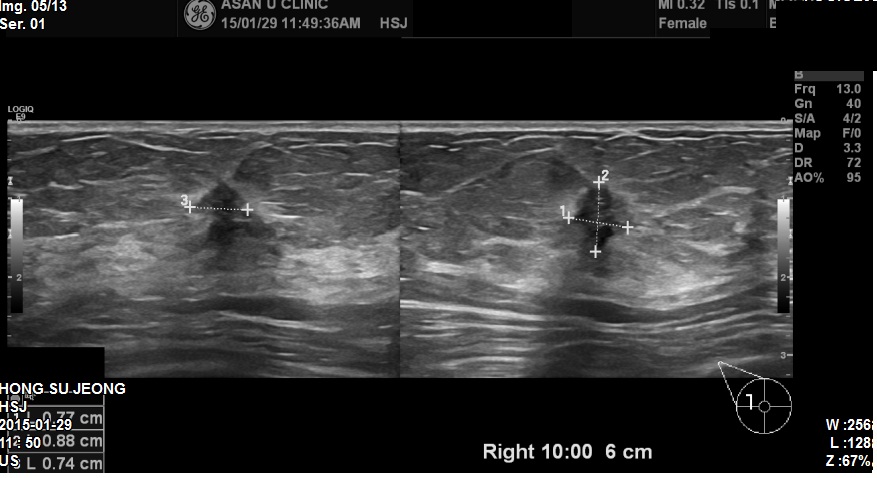

아산유외과 개원후 212번째 유방암진단

건강검진상 유방에 이상소견있다고 조직검사 의뢰되신

60세 여성분입니다.

내원당시 우측 유방 10시 방향과 11시방향에 각각 혹이있었고

두개의 혹모두 악성결절의심되어

조직검사 시행하였으며

10시방향에 혹은 침윤성 유관암, 11시방향에 혹은 상피내암으로 진단되었습니다.

향후 PET scan과 유방 MRI로 더 정밀 검사 할 예정이며

평균수명이 길어져서

나이와 상관없이 적극적 치료를 고려할 것입니다.

빠른쾌유를 기도하면서요.